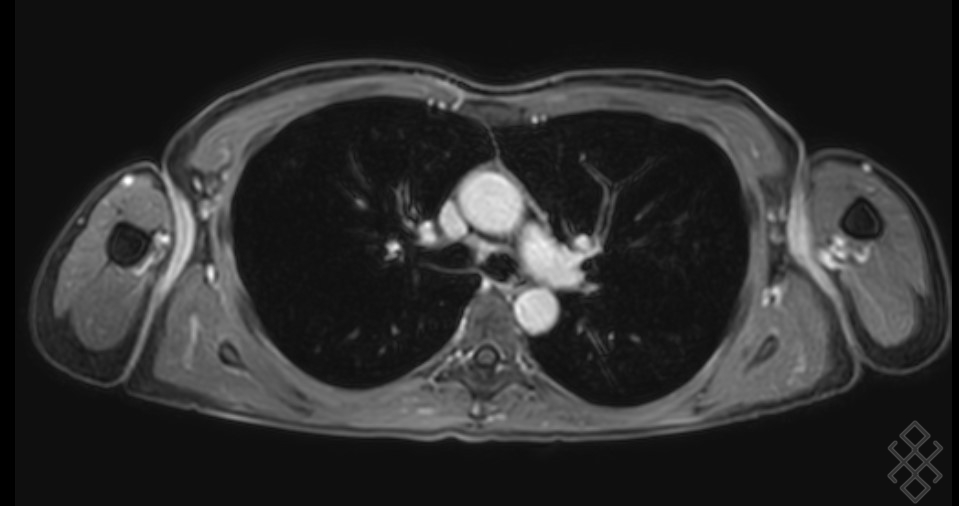

Image IRM normale du mediastin :

l’IRM

du thorax est limité et ne permet pas d’explorer fiable le

parenchyme pulmonaire en routine clinique, Ses indications

sont en bien établies dans la pathologie pleurale,

médiastinale et vasculaire thoracique. La contraste

l’IRM se mis à profit pour caractérisation tissulaire des

tumorales, et pour l’étude de l’envahissement de la paroi

thoracique et des organes de voisinage .

Image radiologique IRM normale

du thorax et de mediastin en coupe axiale pondere

sur T1 FS gadolinium |